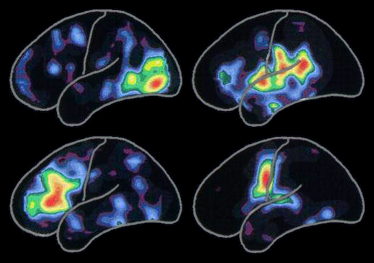

오랜 시간의 경험을 통해서 우리는 신경의 신호의 종류와 그 강도의 패턴을 만들수 있었습니다. 이 패턴들은 세포 단위 수준에서 우리의 뇌가 생각, 기억, 기술, 인식(認識)을 어떻게 기호화 하는지를 설명해주고 있습니다. 왼쪽에 보이는 양전자 방출 단층 촬영사진은 아래와 관련된 뇌 활동의 전형적인 패턴을 보여주고 있습니다.

빨간 부위가 가장 뇌의 활동이 활발한 부분이고 노란색부터 푸른 보라색 순으로 점점 활동이 줄어듭니다.

특정한 활동의 패턴은 새로운 사람과의 만남, 새로운 경험 그리고 새로운 기술습득과 같은 생활의 활동을 통해서 변화됩니다. 그 패턴들은 알츠하이머 병이나 그와 관련된 질병이 신경세포의 활동과 그 세포들의 연결을 방해할때 또한 변화됩니다.